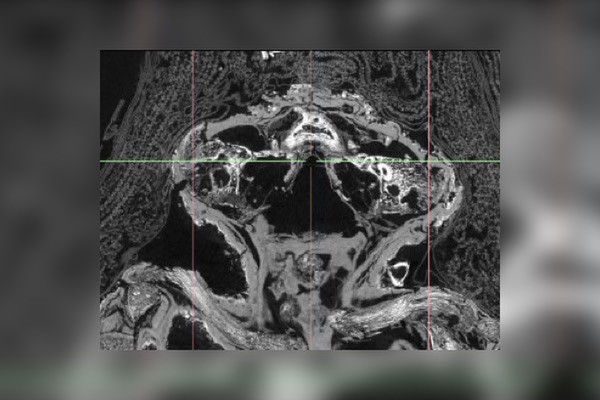

然而這個嬰兒並非健康完整的,而是看起來「胎死腹中」來不及見到美好世界的孩子。這個已經2100年的鷹木乃伊,團隊使用電腦掃描後發現,裡面裝著的是先天性無腦畸形症的嬰兒,也就是所謂腦部跟頭骨發育殘缺的狀況。從外盒來看,這具木乃伊像是一隻老鷹,新奇的外型在1925年曾經被捐到英國梅德斯通博物館。

當時研究團隊的Andrew Nelson教授提到,裡面的嬰兒大概是在23~28周死亡,之後被做成木乃伊,外盒上有著冥界之神歐西里斯躺在停屍架上,女神伊希斯和奈芙蒂斯則站在他的身旁。甚至有許多人認為,這一具木乃伊有法力,因為「胎兒是屬於某種力量。」